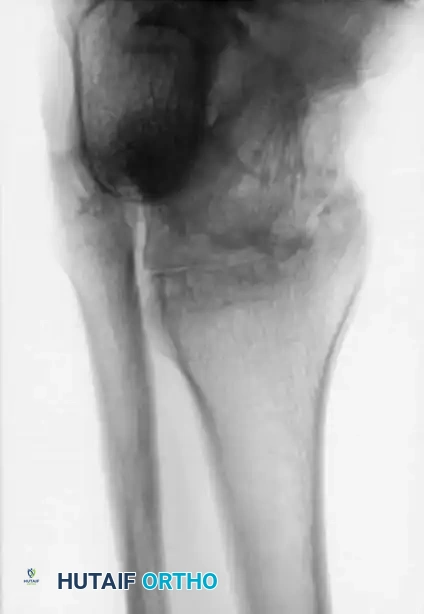

Image

Advanced hemophilic arthropathy of the ankle often requires aggressive intervention. When arthroscopic synovectomy fails to control symptoms in end-stage disease, definitive stabilization via ankle arthrodesis utilizing rigid internal fixation becomes necessary to eliminate pain and prevent further hemorrhagic episodes.